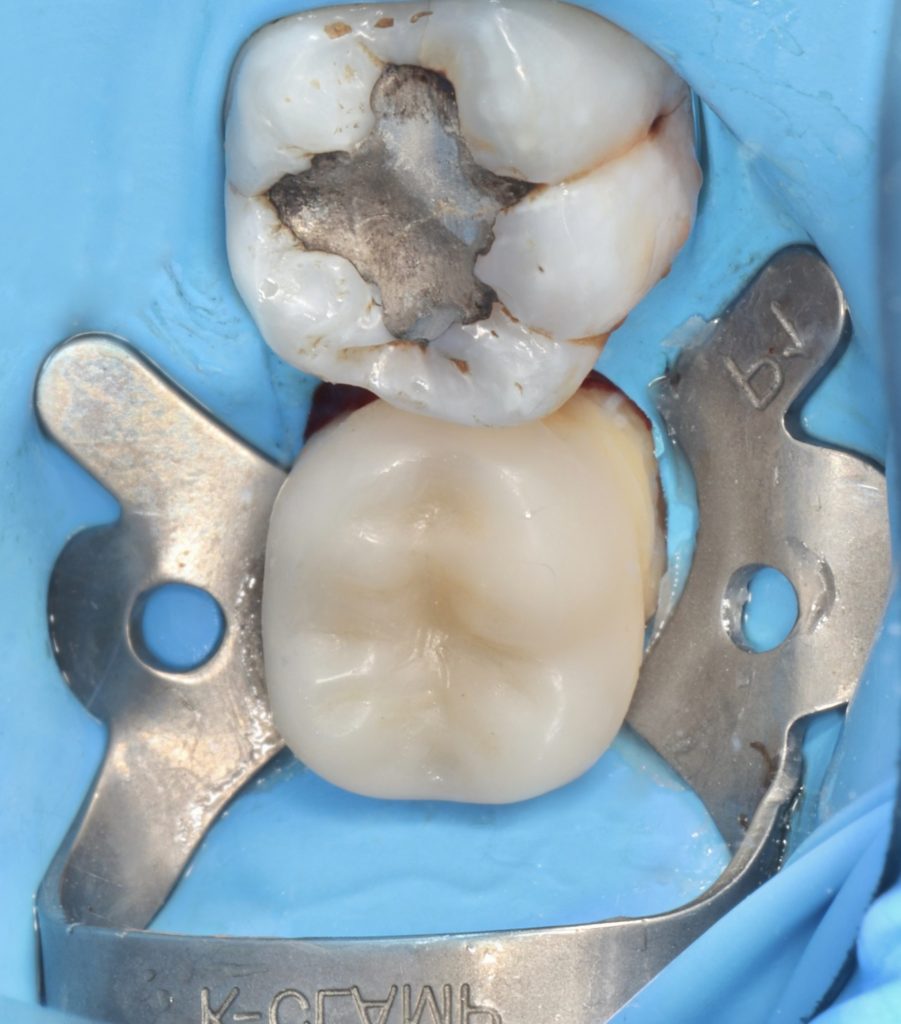

Fiber materials were used to strengthen the furcation area prior to the biobase.The patient’s high saliva density made it necessary to use an intraoral scanner on a rubber dam

3.Fiber reinforced bio base